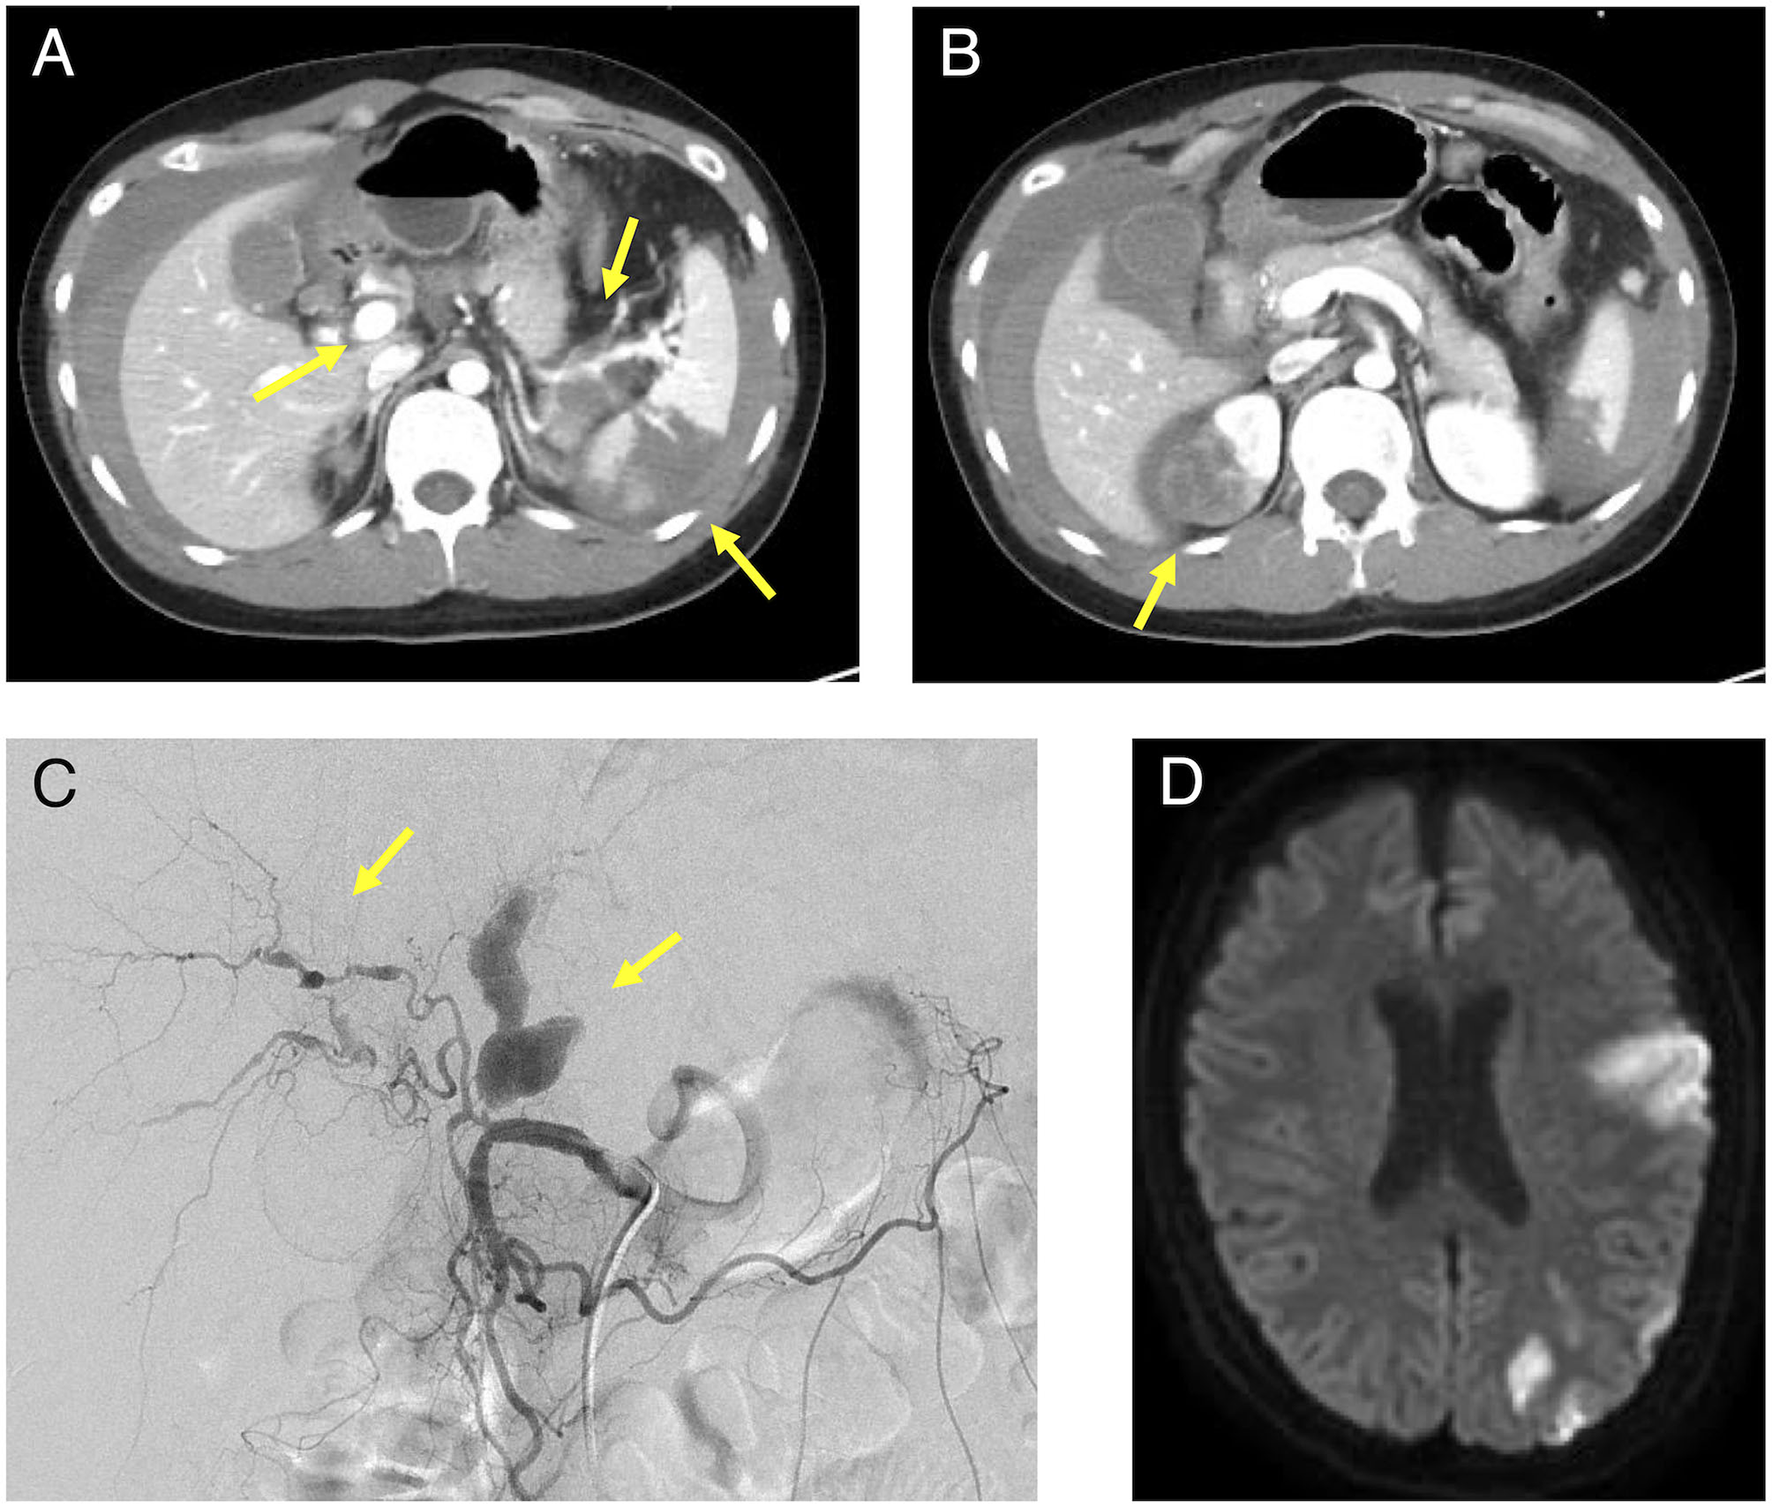

His medical history included bronchial asthma in childhood, ventricular septal defect, osteoma ossificans, and herpes zoster. Additionally, his family history included a grandmother with spinocerebellar degeneration, a grandfather with hypertension, a father with rheumatoid arthritis and dyslipidemia, and a mother with diabetes mellitus. Further, there was no family history of EDS, other genetic diseases, or sudden cardiovascular death in relatives. The patient showed no difference in blood pressure in the upper extremities. The neurological findings included a complete paralysis of the right upper and lower limbs and dysarthria. No other findings were observed in the remaining physical examinations. Blood tests revealed a markedly elevated inflammatory response with a white blood cell count of 38,000/μL (neutrophil: 99%, lymphocyte: 1%) and CRP of 5.02 mg/dL. All autoantibodies and blood culture test results were negative. A transthoracic cardiac ultrasound revealed no vegetation. Contrast-enhanced CT and angiography showed multiple aneurysms of the hepatic, splenic, right renal, left common iliac, and right internal iliac arteries, as well as infarction of the spleen and right kidney with intra-abdominal bleeding (Figures 1A–C). The hepatic aneurysm was enlarged compared to those taken at another hospital 1 week prior (from 13.6 × 7.8 to 16.5 × 13.0 mm). No vascular occlusion was observed on the contrast-enhanced CT scan. Contrast-enhanced magnetic resonance imaging (MRI) of the head and neck showed infarction of the left middle cerebral artery region (Figure 1D) and left internal carotid artery aneurysm, stenosis, and dissection (Figure 2A). Contrast enhancement was observed around the stenotic area; however, a positron emission tomography (PET) scan of the entire body 1 week after starting the treatment revealed no abnormalities. In other words, rupture of the aneurysm leading to intra-abdominal bleeding and stroke-induced progression of vascular stenosis were observed in a short period. IVR was performed shortly after admission. Embolization was performed to treat the hepatic and splenic artery aneurysms, and the bleeding stopped. Although vEDS was a differential diagnosis, the patient had a severe inflammatory response, probably due to vasculitis.

Figure 1

Contrast-enhanced CT, angiography, and head MRI of the patient. (A): Intra-abdominal hemorrhage, splenic infarction, and hepatic and splenic artery aneurysm were observed in the area indicated by the arrow and (B): Right renal infarction was observed in the area indicated by the arrow on the contrast-enhanced abdominal CT. (C): A proper hepatic artery aneurysm was observed in the area indicated by the arrow on angiography. (D): A cerebral infarction was observed in the left middle cerebral artery territory on the plain MRI of the brain. MRI, magnetic resonance imaging; CT, computed tomography.